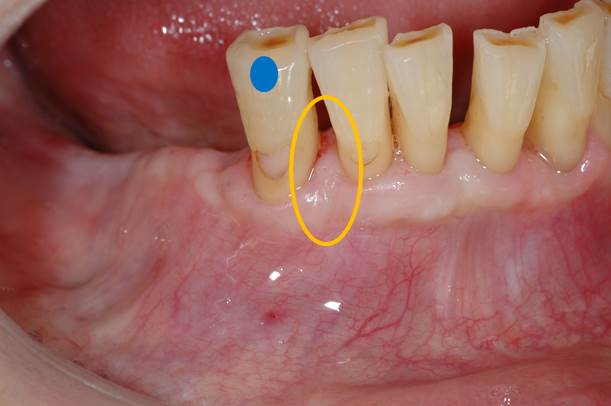

今回は歯周外科処置の中でも最も基本的なフラップ手術の紹介です。

青の歯のオレンジ部分に7mmの歯周ポケットが存在します。

歯肉を剥離して、掃除が終了した状態です。(オレンジの点線部分が失われた歯槽骨)